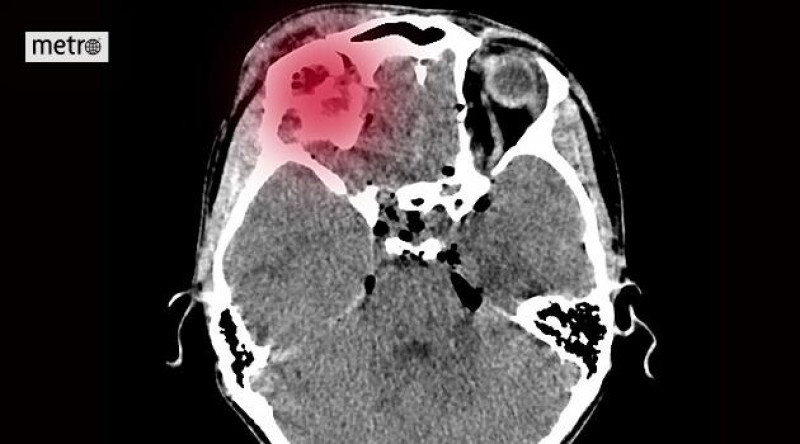

Do nemocnice přišel čtyři hodiny po mrtvici. Přerov má vlastní iktové centrum a šetří čas

Na prahu sedmdesátky ženě najednou znehybněla polovina těla, ochrnula na pravou ruku i nohu. Zavolala si záchranku a ta ji okamžitě převezla do přerovské nemocnice.

V Orlickoústecké nemocnici vzniklo centrum vysoce specializované iktové péče

Společnost Nemocnice Pardubického kraje (NPK) rozšířila svou síť center vysoce specializované péče o pacienty s cévní mozkovou příhodou o Orlickoústeckou nemocnici.